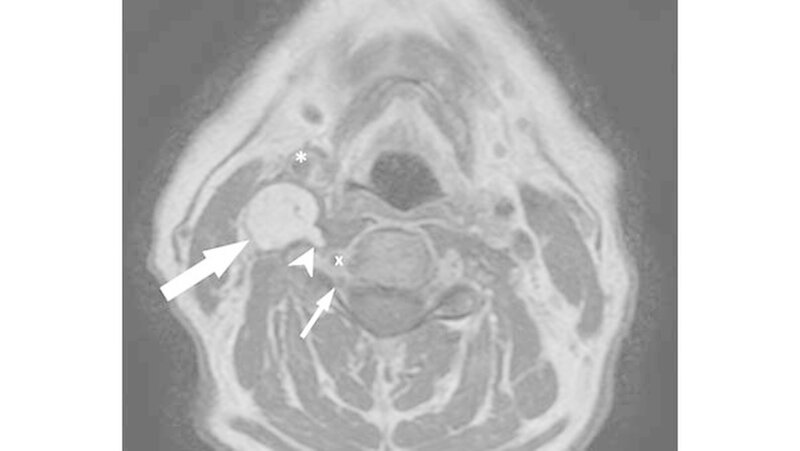

Im MRT zeigte sich korrelierend zum Tastbefund eine spindelförmige Raumforderung mit den Ausmaßen von 5x2x2cm paravertebral auf Höhe HWK 3 bis HWK 6 (Abbildung 1). Der Befund verdrängte sowohl den prävertebrale M. longus colli als auch die Arteria carotis nach ventral.

Die Vena jugularis interna war subtotal komprimiert. Kleinere Ausläufer der Raumforderung lagen unmittelbar lateral des Neuroforamens der Radix C5, unterhalb des HWK 4 und reichten bis auf 3mm an die Arteria vertebralis heran (Abbildung 2). Ein infiltratives Wachstum war radiologisch nicht nachweisbar.